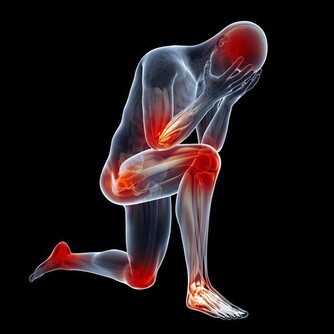

跌倒不但會造成腦部受傷、骨折等嚴重外傷,還會引發“跌倒恐懼症”,給老人帶來極大的心理創傷。

1.跌倒造成身體器質性傷害

跌倒損傷最嚴重的是髖部骨折,成為老年人首位傷害死因。

另外會造成顱腦損傷,可直接導致死亡。